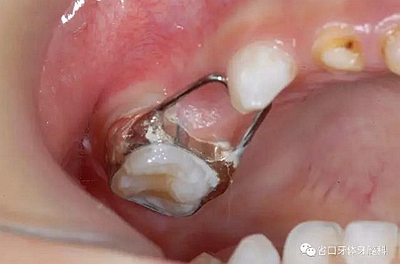

带环丝圈式保持器

试戴合适后用玻璃离子粘接,粘接后注意检查是否有咬合高点

全冠或带环丝圈式保持器:由不锈钢丝制成,靠一个戴在缺隙旁边牙齿上的牙冠或是带环固定。钢丝与带环或全冠连接,沿着空隙的两侧延伸到另一颗牙齿上,这样就能起到保持间隙的作用。使得恒牙有足够的间隙长出而不发生拥挤。